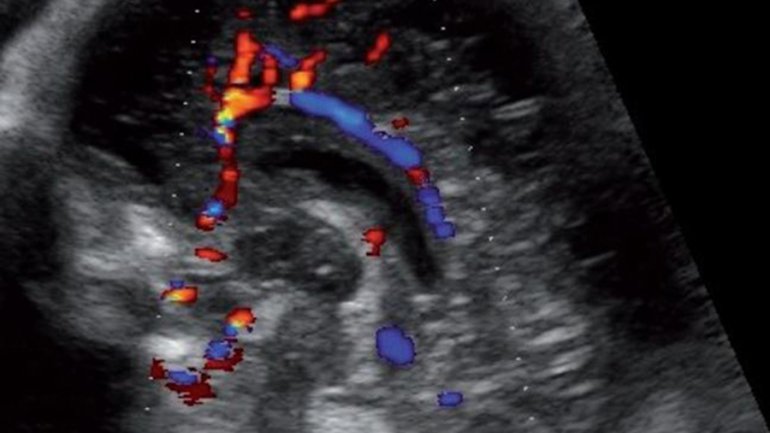

Ultraschall 27. SSW

Mit dem Dopplerultraschall kann auch der Blutfluss in den Blutgefäßen im Gehirn farbig dargestellt werden. Der*die Arzt*Ärztin überprüft so Reifung und Durchblutung des Gehirns und kann darüber bestimmte Krankheiten erkennen oder ausschließen.